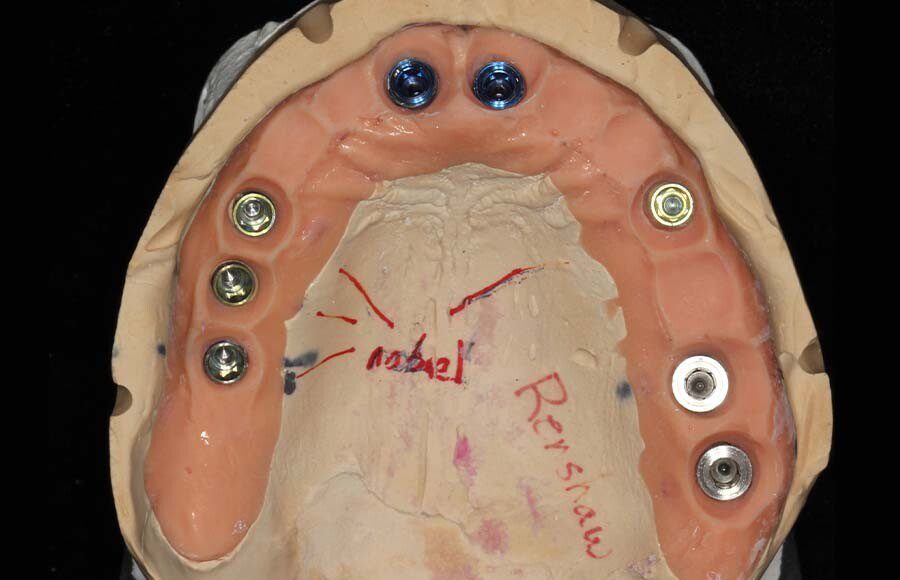

Smile GalleryImplant RestorationsFull Mouth Implant Restoration Full arch zirconia implant bridge (full smile) 1 of 37 Pre-op full smile Pre-op lips retracted Pre-op panoramic x-ray Extraction of strategic teeth Placement of implants Extraction of some remaining teeth after verification of adequate implant stability Occlusal view Post-op panoramic x-ray Immediately fabricated provisional restoration (tissue side view) Immediately fabricated provisional restoration (occlusal side view) Immediate provisional delivered on day of surgery Immediate provisional 2 weeks later Scalloped tissue developed from the provisional at 2 weeks Jig used for making a master impression Provisional in place (full smile) Provisional in place (lips retracted) Provisional in place (right side) Provisional in place (left side) Wax try-in (full smile) Wax try-in (right side full smile) Wax try-in (left side full smile) Wax try-in (full face, lips together) Wax try-in (full smile) Wax try-in (right side) Wax try-in (left side) Wax try-in (lips retracted) Full arch zirconia implant bridge on master cast (frontal view) Full arch zirconia implant bridge on master cast (occlusal view) Implant positions and soft tissue representation on master cast (occlusal view) Soft tissue representation on master cast (frontal view) Full arch zirconia implant bridge (tissue side view) Soft tissues on day of delivery (occlusal view) Soft tissues on day of delivery (frontal view) Full arch zirconia implant bridge delivered (lips retracted) Full arch zirconia implant bridge (lips retracted, close up) Post treatment panoramic x-ray Full arch zirconia implant bridge (full smile)